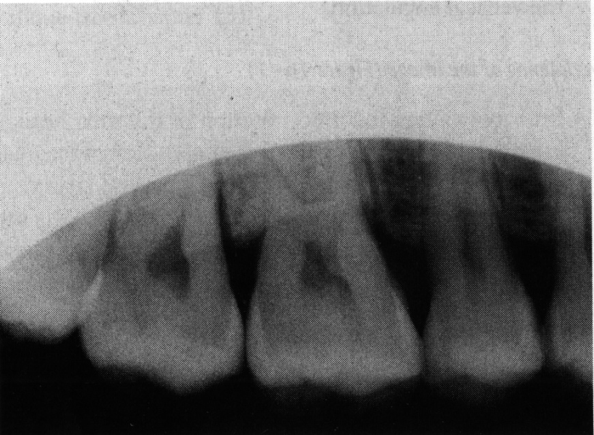

Dens in dente